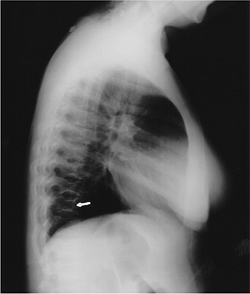

Pulmonary involvement (bilateral hilar

and right paratracheal adenopathy with or without infiltrates) is

common (90%), but patients may be asymptomatic. -

![]() |

|

FIGURE 15-42 Sarcoidosis. (A) PA radiograph of the chest showing bilateral hilar and right paratracheal adenopathy. Note the tracheal deviation (arrows). (B)

Radiograph of the right hand showing lacelike trabecular pattern and cystic changes in the third middle phalanx and fourth proximal phalanx. |